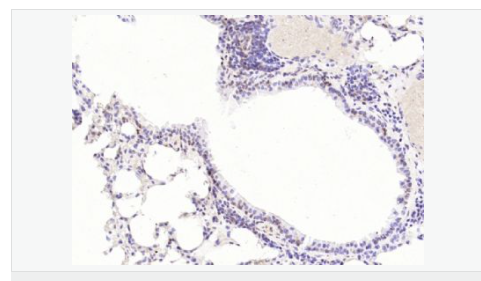

| 產(chǎn)品應(yīng)用 | WB=1:1000-2000 ELISA=1:1000-5000 IHC-P=1:100-500 IHC-F=1:100-500 Flow-Cyt=1ug/Test ICC=1:100-500 IF=1:100-500 (石蠟切片需做抗原修復(fù)) not yet tested in other applications. optimal dilutions/concentrations should be determined by the end user. |

| 細(xì)胞定位 | 細(xì)胞核 細(xì)胞漿 |